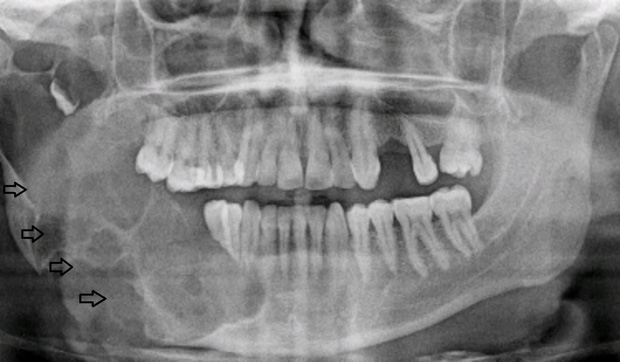

Theo chia sẻ từ Long Chun, sau buổi ghi hình số thứ 4 của chương trình, anh chàng đi khám và phát hiện bên xương hàm phải có một khối u khá lớn và nó đã ăn vào gần như hết vùng xương hàm bên phải. Ngay lập tức, Long Chun phải đặt vé máy bay trở về Hà Nội để kiểm tra chính xác tình trạng bệnh mà mình đang gặp phải. Kết luận cho thấy, Long Chun có một khối u nguy hiểm mang tên u men xương hàm. Nếu để lâu mà không điều trị ngay thì khối u có thể ăn vào máu và làm tăng nguy cơ mắc ung thư máu cao.

U men là loại u khá phổ biến ở vùng xương hàm mặt (tên gọi đầy đủ là u nguyên bào tạo men - Ameloblastoma). Bệnh thường gặp ở những người trẻ từ 20 - 30 tuổi, chiếm tỷ lệ khoảng 50% trong tổng số các loại u lành tính của xương hàm mặt (không kể nang do răng), có nguồn gốc từ các tế bào tạo ra men răng.

- Ở giai đoạn sớm: khối u phát triển chậm, âm thầm và không có triệu chứng cụ thể nên thường chỉ phát hiện được khi tình cờ chụp X-quang kiểm tra. Dù vậy, nếu chỉ dựa vào phim X-quang để kết luận thì vẫn còn quá sớm, cần kết hợp thêm với kết quả giải phẫu bệnh lý của từng người.

- Ở giai đoạn u men phát triển: bạn có thể gặp phải một số vấn đề ở vùng xương hàm như tê môi cằm, sưng hàm, biến dạng mặt (khiến mặt lệch hẳn sang một bên), răng trên u có thể lung lay hoặc di lệch một ít kèm theo biểu hiện đau nhức, khó chịu và chảy mủ.

- Ở giai đoạn muộn: khối u lúc này đã đạt kích thước lớn, gây phồng xương nhiều nên làm mặt biến dạng rõ, xương bị phá hủy. Lúc này, bệnh nhân cũng cảm thấy đau nhức, răng lung lay nhiều và dễ bị xô lệch hơn.